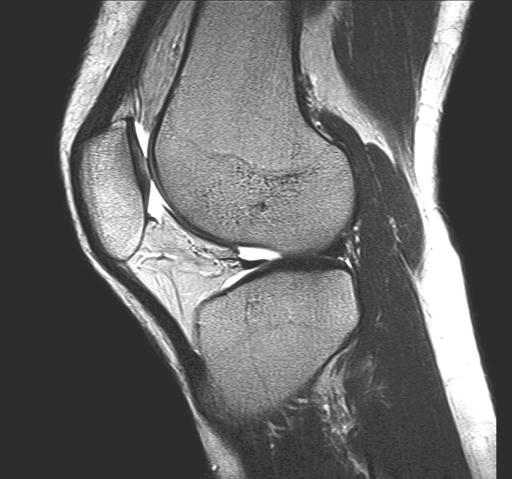

MRT Bild eines Kniegelenks in seitlicher Ansicht

Wegen ihrer hochauflösenden Darstellung von Muskeln, Sehnen, Bändern, Knochen und Knorpel ist die MRT aus der modernen Diagnostik von Erkrankungen des Bewegungsapparates nicht mehr wegzudenken.

Sehnen- und Muskelfaserrisse, Sehnen- und Schleimbeutelentzündungen, Knorpelschäden an den Gelenken, Knochenbrüche, Verschleißerkrankungen und jegliche Entzündungen und Tumoren des Stütz- und Bewegungsapparates lassen sich vorzugsweise mit der MRT abbilden.